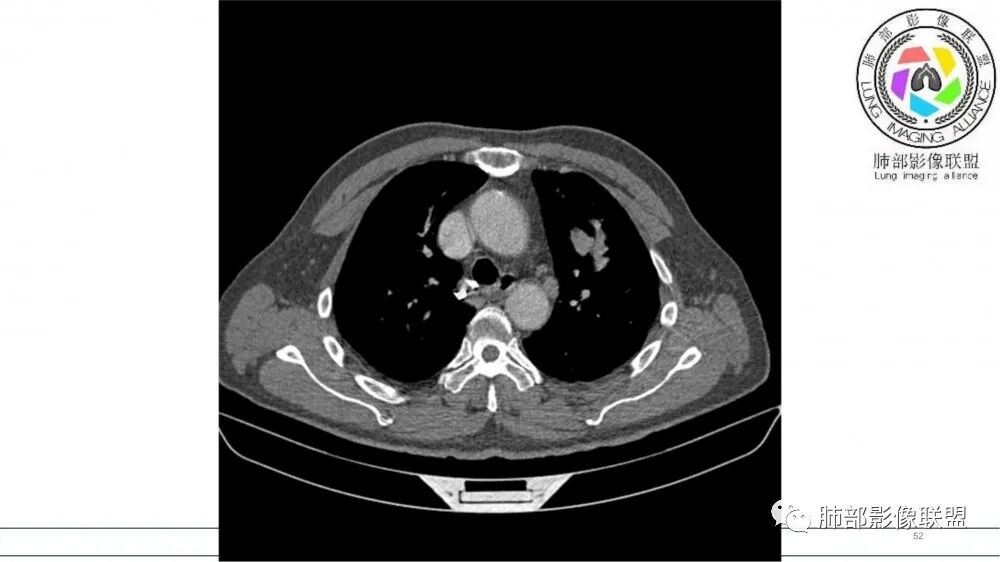

左肺上叶前段支气管内铸形生长软组织影,增强后均匀强化,远侧见斑片状磨玻璃影。考虑恶性病变,粘表?粘液腺?

老年男性,左肺上叶前段支气管内铸形阴影,增强后病灶不均匀强化,内部有坏死?远端可见斑片状阴影(阻塞性肺炎)。考虑恶性病变,老年人,鳞?类癌?粘表不能排除。

男,70岁,吸烟史,咳嗽,胸闷憋气一个月,左肺上叶不规则形软组织密度影,病灶沿支气管走形,周围见粟粒及棉絮样稍高密度影,增强扫描病灶内见少许坏死,考虑鳞癌可能,鉴别结核。

老年男性,肺气肿,吸烟史,左肺上支气管腔内铸型高密度影,呈指套状,远端多发树芽,增强不均匀强化,考虑鳞癌,鉴别小细胞癌

2021年8月6日晨读病例结果:小细胞肺癌

指套征:是影像征象,胸部平片表现为手指状密度增高影,以肺门为中心呈放射状分布,CT显示扩张支气管内低密度黏液栓形成或实性病变,呈管状、树枝状或卵圆形密度增高影;支气管扩张伴近端梗阻时,扩张支气管内部黏液分泌物不能排出而形成。可以伴随远端空气潴留征、阻塞性炎症。

研究报道,中心型 SCLC 经 CT 扫描后通常支气管表现为鼠尾样狭窄,肺门或纵隔肿块明显,由于肿块沿管壁生长表现为顺延支气管形态的不规则形状。病灶相对特征性影像学表现比如鸭蹼状、腊肠状、葫芦状及葡萄状改变,可以出现血管包埋,很少有空洞、空泡,较少引发肺不张,阻塞性炎症成都较轻。与一般肺癌比较,恶性程度高,侵袭力强、病灶很小就容易远处转移!Herzberg 等[19]研究指出,20%以上 SCLC 倍增时间短,预后不良。